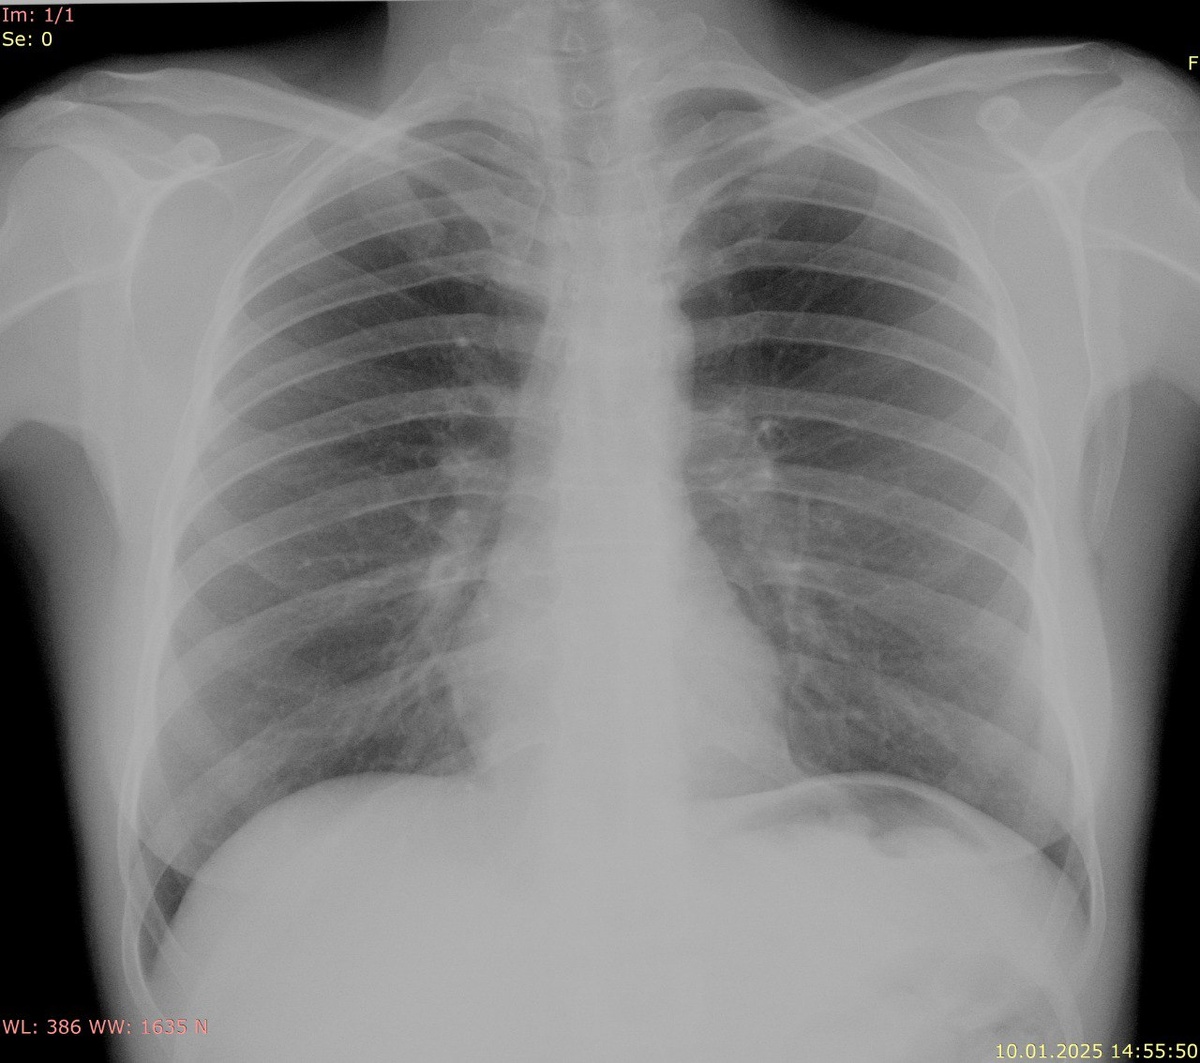

3. Качество изображения: Рентгенография обеспечивает более высокое качество изображений с лучшей контрастностью и четкостью, что позволяет выявлять мельчайшие изменения в легочной ткани.

1. Рентгенография: Результаты интерпретируются рентгенологом, который тщательно изучает снимки на наличие изменений, таких как тени, затемнения или увеличения органов. Заключение бывает более детализированным.